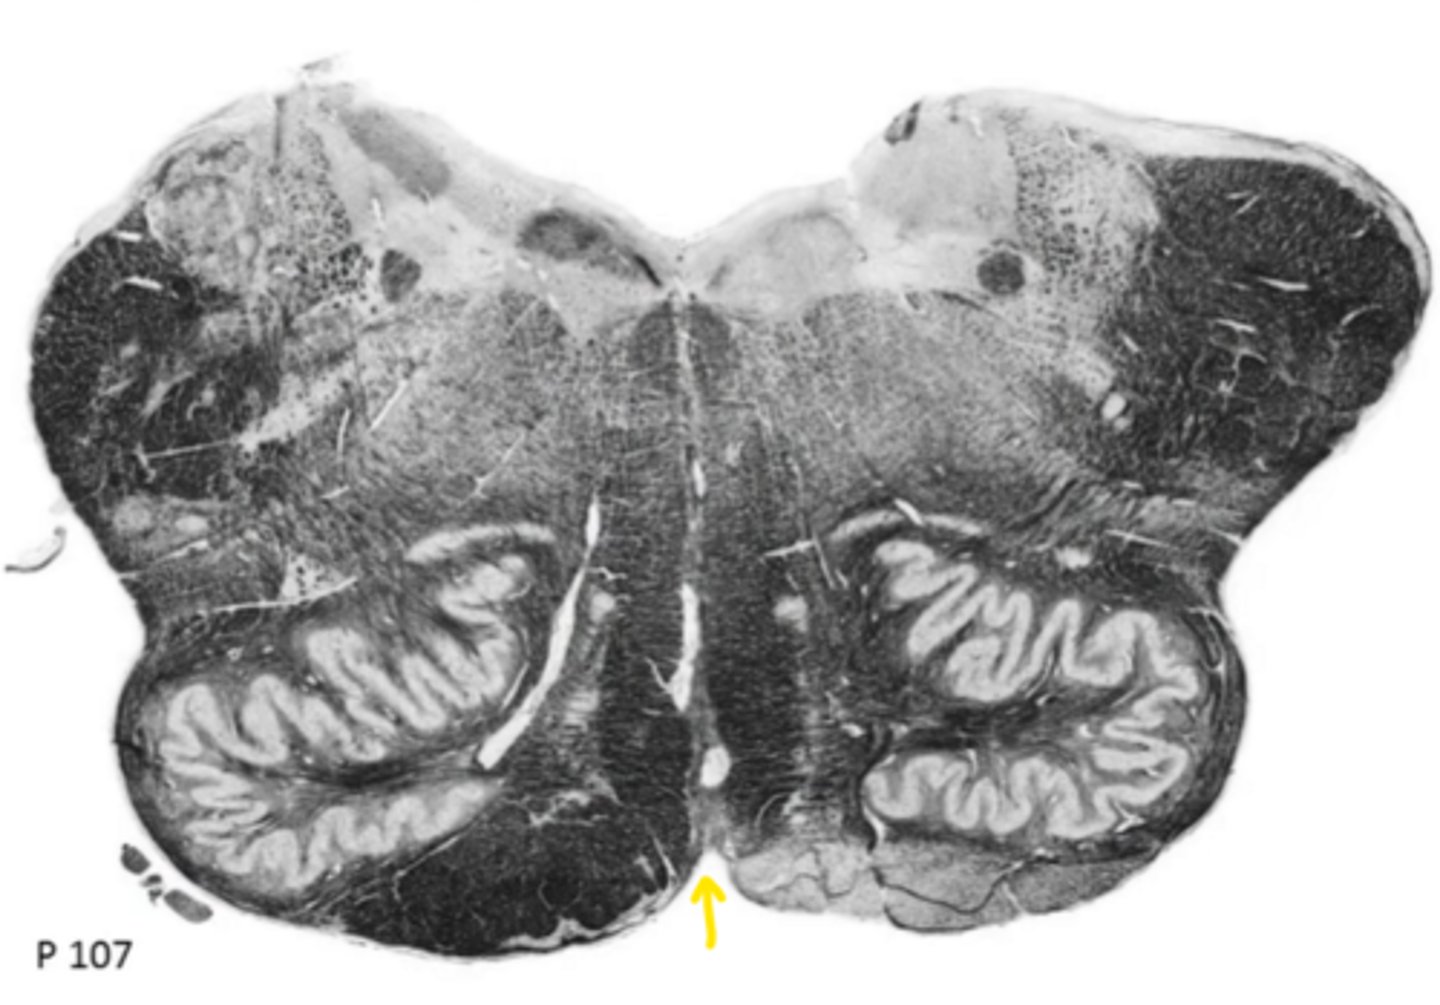

central canal

ID the space

central gray

ID the structure

hypoglossal nucleus

ID the nucleus

gracile nucleus

cuneate nucleus

inferior cerebellar peduncles

reticular formation

internal arcuate fibers

ID the fibers

principle olivary nucleus

medial lemniscus

corticospinal fibers

anterior median sulcus

posterior median sulcus